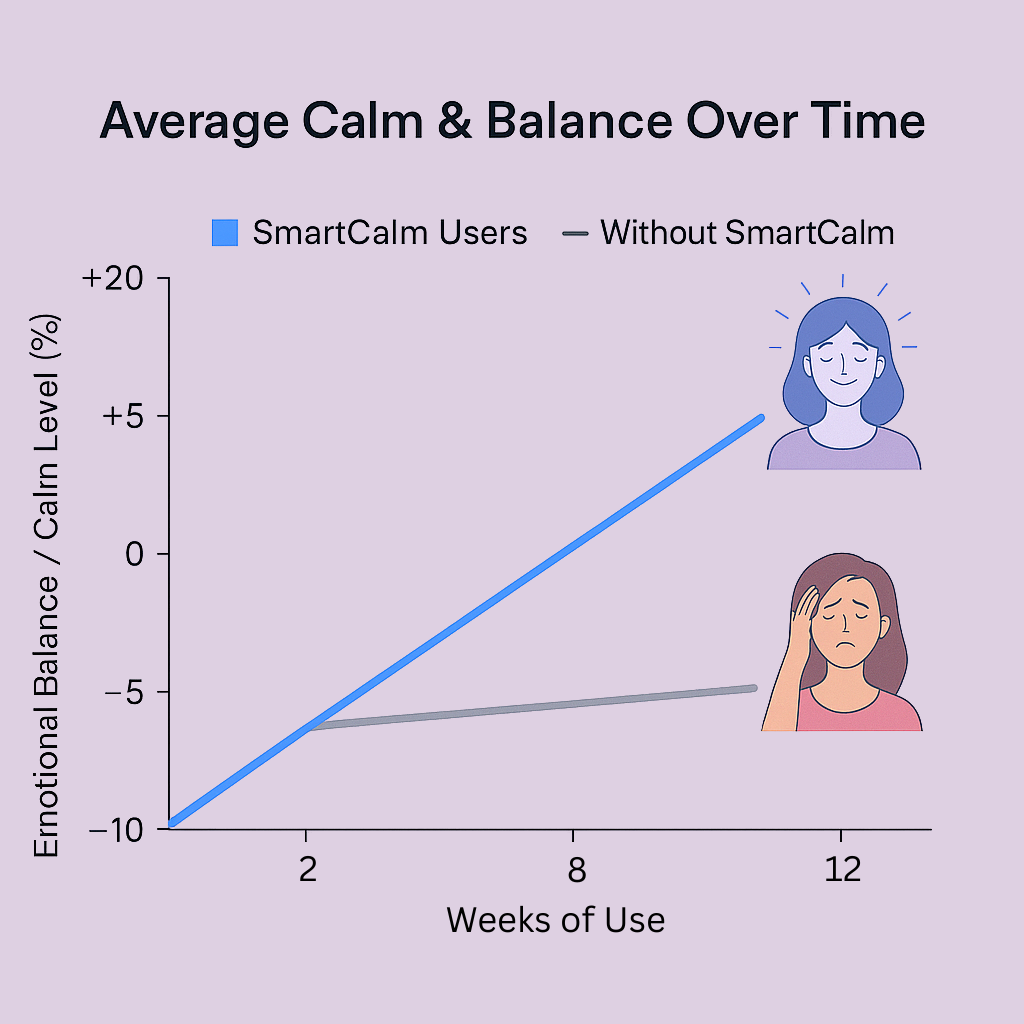

Your calm and energy over time, with SmartCalm™ vs without

Your calm and energy over time, with SmartCalm™ vs without

In the first 90 days, you’ll feel your calm return, and your energy rise.

In the first 90 days, you’ll feel your calm return, and your energy rise.

In the first 90 days, you’ll feel your calm return, and your energy rise.